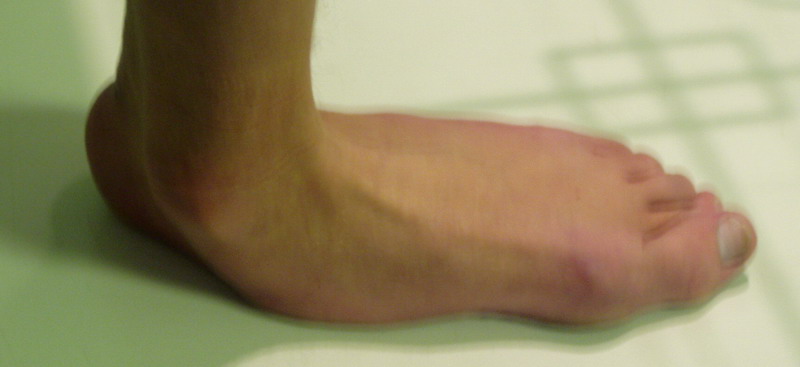

Пациент 15 л., болезнь Литтля, спастический нижний парапарез, интеллект высокий. Ребенок настроен на активный образ жизни. С недавнего времени начал ходить без дополнительной опоры. Появилась проблема с левой стопой - во время ходьбы опора приходится на смещенную кнутри таранную кость.

Может образоваться болезненный натоптыш или язва.Общепринятой операцией является трехсуставной артроде с мобилизацией таранной кости. Выполнять такую операцию у спастика и в раннем возрасте проблематично. Родстьвенники тем более готовы материально и морально осуществить хирургическое лечение за рубежом, если оно показано и возможно.Предпочтительно в Австрии и Германии. Если кто-то посоветует координаты таких клиник - были бы признательны.

В приводимом случае, 15 летнему больному показан 3-суставной артродез. Однако считаю нецелесообразным существенно менять конфигурацию стопы, поскольку плоско-вальгусные деформации стоп это компенсаторный ответ на сгибательно-приводящие установки нижних конечностей. Изменение положения стоп(коррекция пронации) может нарушить сложившийся стереотип ходьбы, и ухудшить ситуацию.